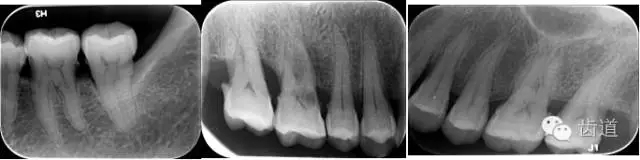

6、輔助檢查

X線:根尖片、曲面斷層片(牙槽嵴頂,水平垂直吸收,程度)

21.webp.jpg

22.webp.jpg

23.webp.jpg